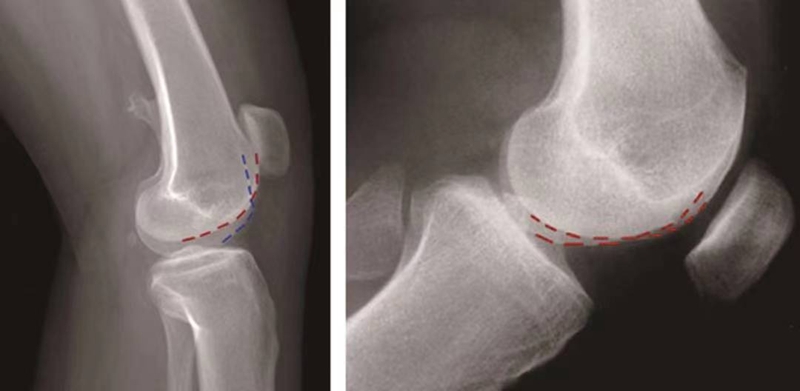

①交叉征:

H.Dejour在1987年介绍了股骨滑车发育不良在膝关节标准侧位X线片的特殊表现,描述了交叉征(crossing sign)。在股骨滑车发育不良的膝关节标准侧位像上,股骨滑车沟基底线会与股骨外髁的轮廓线相交叉,即为交叉征(图11),意味着股骨滑车发育平坦。

图11 交叉征

③双轨征(或称为双线征):

是指在膝关节标准侧位像上,代表股骨内外侧滑车的两条线分开,呈双轨样(图13)。它的出现提示股骨内侧滑车发育低平,导致它的前缘出现晚于外侧滑车。

图13 双轨征

(3)股骨滑车发育不良的分型:

1996年,D.Dejour和B.Le Coultre提出了更准确的股骨滑车发育不良的四种分型(图14):

图14 股骨滑车发育异常分型 A型:交叉征;B型:交叉征+突起征;C型:交叉征+双线征;D型:交叉征+突起征+双线征